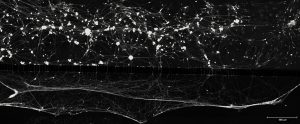

TÍTULO DE LA IMAGEN (traducido por la organización): Un árbol neuronal de frío, dolor y placer

AUTOR: David Cabañero

TEXTO ARTÍSTICO-DIVULGATIVO

(traducido por la organización) Una Sensación de Frescura. En un ratón modificado genéticamente, las neuronas que perciben el frío forman un «árbol neuronal» que brilla en verde gracias a una proteína fluorescente ligada al TRPM8, el principal receptor del frío. Mientras tanto, en rojo se tiñen las neuronas grandes involucradas en la percepción sensorial rápida. La mínima superposición de rojo y verde resalta el papel de las neuronas del frío en las sensaciones más lentas que a menudo involucran dolor o placer. Esta vibrante imagen muestra cómo el frío moldea nuestras emociones, desde el agudo pinchazo del frío hasta el placentero frescor.